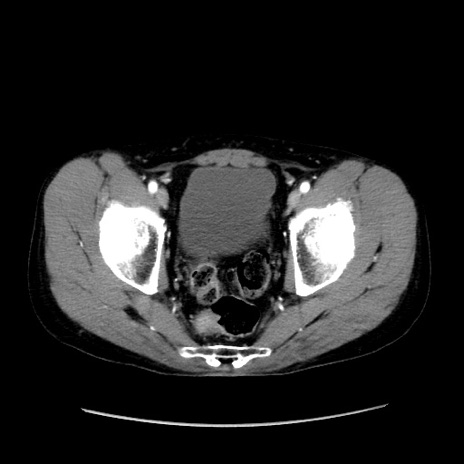

冠状断像

症例37(横断像)

【症例】40歳代 男性

【主訴】腹痛

【現病歴】4時間ほど前に電車に乗車中に臍部上より腹痛出現。徐々に増悪し起立困難となり、救急外来受診。生ものは数日食べていない。今朝お雑煮を食べた。

【身体所見】BT 36.8℃、BP 117/84mmHg、HR 91/min、SpO2 97%、苦悶様、腹部:臍上部広範囲圧痛あり、反跳痛±

【データ】WBC 8100、CRP 0.03